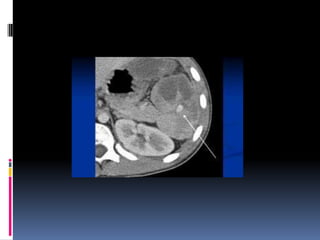

¿LÍQUIDO LIBRE HIPERDENSO?

Diagnóstico: RUPTURA VESICAL

¿LÍQUIDO LIBRE HIPERDENSO? Diagnóstico: RUPTURA VESICAL